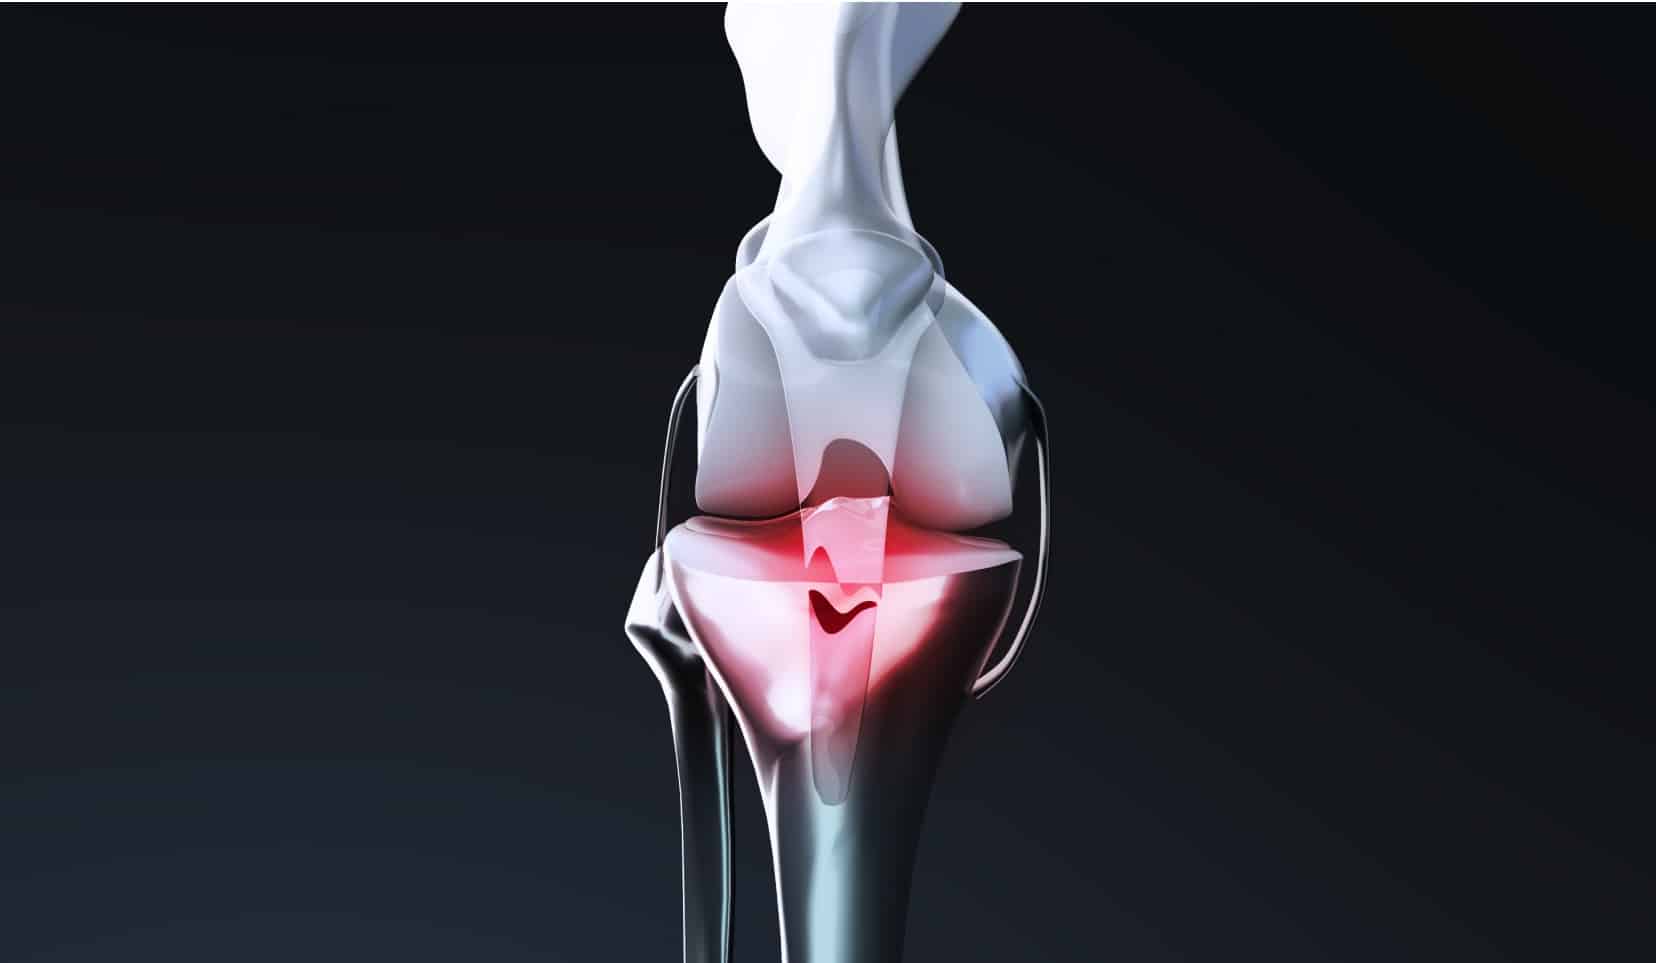

Qu’est-ce qu’une rupture du tendon rotulien et du tendon quadricipital ?

Les tendons permettent aux muscles de bien s’insérer sur les différentes parties osseuses de l’articulation. Ils font partie des structures qui servent à stabiliser les articulations et à réaliser des mouvements comme la flexion ou l’extension.

Le tendon rotulien et le tendon quadricipital sont les deux tendons principaux du genou.

Le tendon rotulien se situe à l’avant du genou, entre les muscles jambiers et la rotule. Son rôle majeur est d’assurer la transmission au tibia des actions exercées par le quadriceps.

Le tendon quadricipital se situe aussi à l’avant du genou, mais entre le muscle du quadriceps et la rotule. Son rôle majeur est de permettre à un individu de réaliser les mouvements de flexion et d’extension de la jambe, ainsi que de se tenir debout.

La rupture du tendon rotulien ou du tendon quadricipital est l’interruption partielle ou complète de sa continuité. Il s’agit d’une pathologie rare qui touche surtout les personnes âgées de plus de 40 ans ayant subi un traumatisme violent. Les tendinites peuvent accentuer cette pathologie.

Un tendon rompu entraîne un gonflement rapide et important au niveau de la rotule, ainsi qu’une douleur intense, une impotence fonctionnelle importante, et une translation de la rotule.